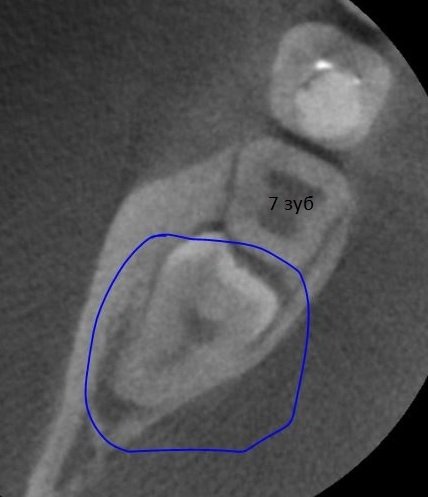

На протяжении трёх дней беспокоила несильная ноющая боль с правой стороны внизу. Сделали снимок, врач предположил, что боль возникает из-за зуба мудрости, который ещё не прорезался. И сразу записала на удаление.

Не знаю, можно ли что-то понять по приложенному снимку, но сколько примерно занимает удаление такого зуба и обязательно ли это?

Однозначно, причина беспокойств — это неправильно расположенная восьмёрка. Удаление необходимо, в противном случае мы получим скученность всего зубного ряда и потеряем седьмой зуб. Удаление сложное и требует профессионализма и опыта. Потребуется моя помощь — запишитесь к нам на приём к челюстно-лицевому хирургу.